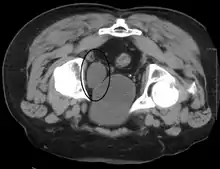

المثانة البولية والبروستاتا مفرطة التنسج (التصوير بالموجات فوق الصوتية).